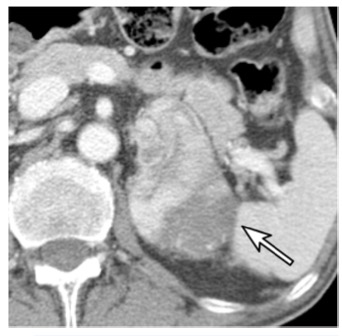

圖 一名67歲的男性,患有乙狀結腸癌。增強CT圖像顯示左側腎上腺有一個74毫米的結節(箭頭)。腎上腺切除術后,該結節被證實為腎上腺皮質癌。結腸癌經息肉切除術后確認為PT1期